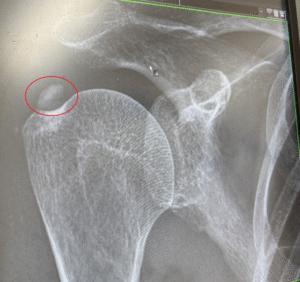

↓ 私の右肩のレントゲンです。赤で〇を付けた部分が石灰化です。

結構大きいですよね(゚Д゚;)

この石灰化が固いものか、柔らかいものかは、

レントゲンやエコーではわからないらしいです。